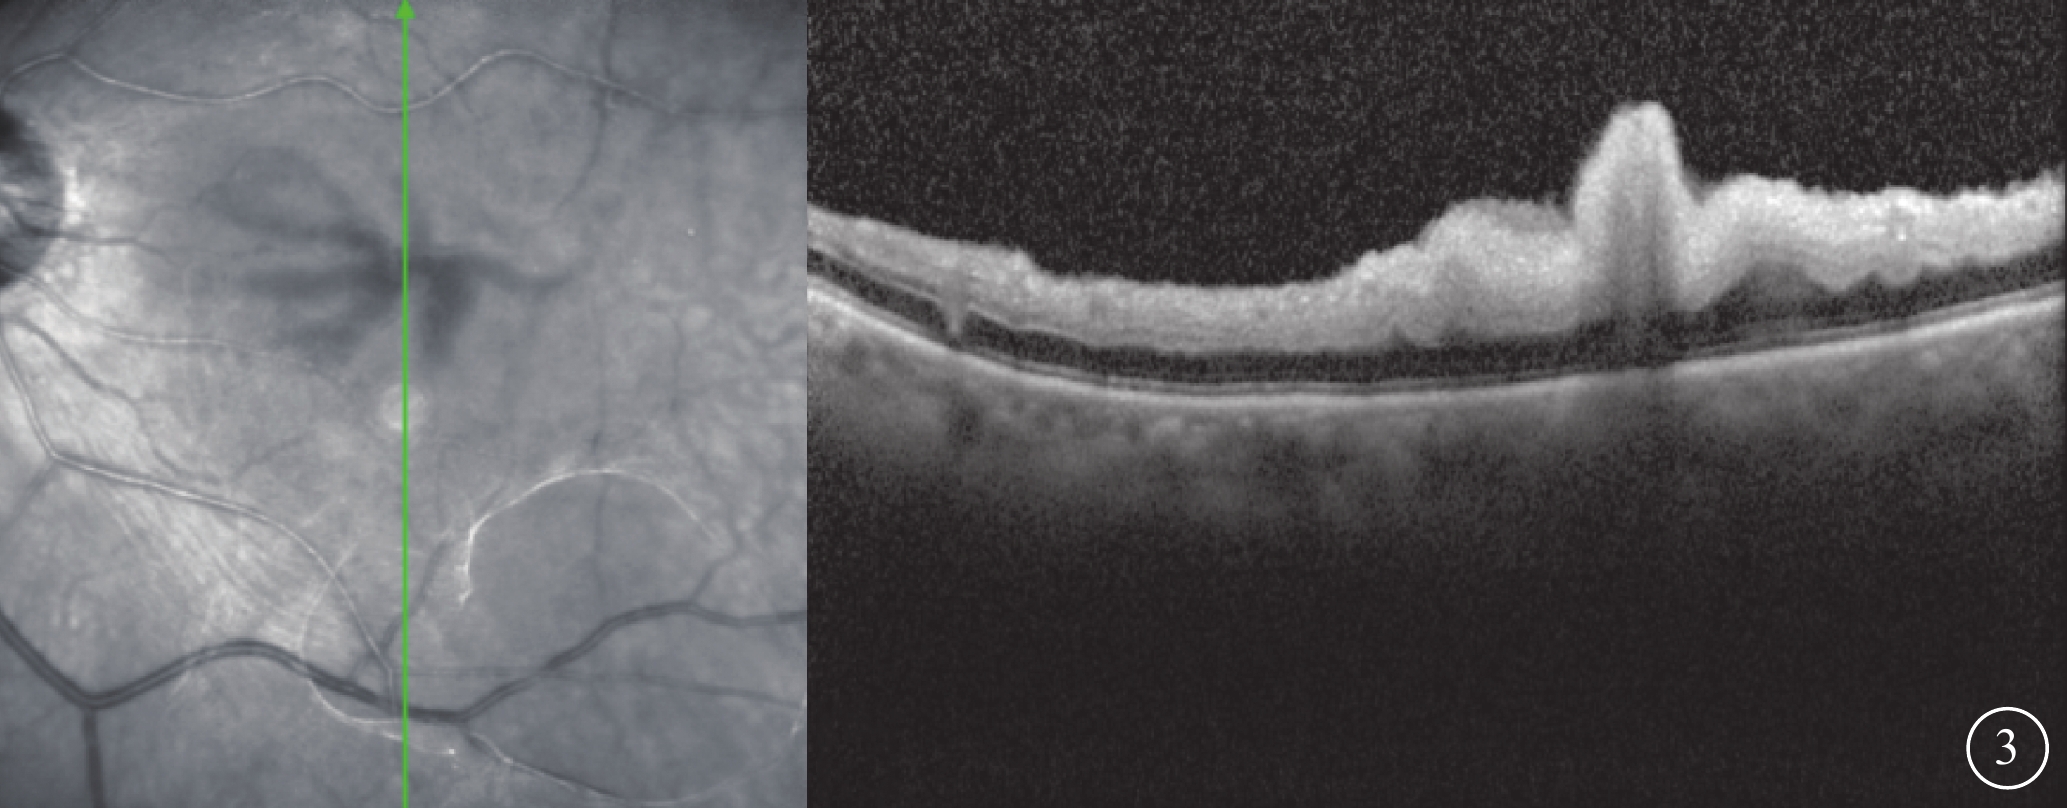

患者女,77歲。因左眼視力下降8個月加重1個月于2017年10月26日至北京大學第三醫院眼科中心就診。既往曾有晨起時一過性左眼黑矇史;否認高血壓、糖尿病等全身病史。甘油三酯輕度升高,出凝血時間正常。眼部檢查:左眼視力0.1,矯正不能提高;右眼視力0.2,矯正視力0.3。左眼眼壓(IOP)20 mmHg(1 mmHg=0.133 kPa)。晶狀體核性混濁;眼底可見黃斑前膜。右眼晶狀體混濁,其余眼前節及眼底檢查未見明顯異常。診斷:(1)左眼白內障;(2)左眼黃斑前膜。于10月28日在局部麻醉下行左眼白內障超聲乳化IOL植入、23G玻璃體切割手術(PPV)。手術參數:超聲乳化瓶高85 cm,PPV時IOP 28 mmHg。手術時間45 min,過程順利。手術后第1天,左眼視力眼前數指。角膜輕度水腫;眼底視盤邊界清楚,色澤正常,黃斑區輕度水腫。IOP 37 mmHg,給予降眼壓藥物控制。手術后第2天,患者自述晨起時左眼黑矇,檢查左眼視力上方眼前手動。眼底視盤邊界清楚,顏色淡;后極部視網膜灰白水腫,無櫻桃紅斑(圖1A),視網膜動脈內血流中斷;視盤鼻側見羽毛狀灰白水腫楔狀區域(圖1B),與視網膜血管分布不一致。IOP 18 mmHg。FFA檢查,視盤和脈絡膜充盈遲緩,視網膜中央動脈14″ 73開始充盈,可見動脈前鋒,21″17靜脈尚未完全充盈;25″92視盤鼻側開始顯現由邊界清楚羽毛狀強熒光拼成的楔形區域,隨時間延長熒光增強,但始終邊界清楚(圖2A)。次日ICGA檢查,脈絡膜充盈遲緩,至10′42″20時視盤鼻側開始出現脈絡膜強熒光區,與FFA所見形態部位一致(圖2B)。OCT檢查,視網膜內層彌漫強反射,層次不清,黃斑中心凹處呈皺褶狀隆起(圖3),鼻側病灶區脈絡膜層面異常反射不顯著。頸動脈彩色多普勒血流顯像(CDFI)檢查,雙側頸動脈硬化斑塊形成。心臟CDFI檢查,左室泵功能正常,舒張功能減低;主動脈瓣輕度關閉不全。神經內科初步診斷:頸內動脈系統短暫性腦缺血發作。頭頸部CT血管造影(CTA)檢查,雙側頸內動脈起始部血管壁混雜斑塊形成,管腔變窄。頭顱CT檢查,多發腔隙性腦梗死,軟化灶。腦白質疏松,腦萎縮。未行頭頸部數字減影血管造影。24 h橈動脈動態血壓監測結果:白天平均血壓121/60 mmHg,脈壓差60.7 mmHg;夜間平均血壓110/51 mmHg,脈壓差59.7 mmHg。最終臨床診斷:(1)左眼脈絡膜三角綜合征;(2)左眼視網膜中央動脈阻塞(CRAO);(3)左眼內低灌注。

左眼手術后第2天OCT像。左圖為掃描部位和方向,右圖為檢查結果。視網膜內層彌漫強反射,層次不清晰,黃斑中心凹處呈皺褶狀隆起

左眼手術后第2天OCT像。左圖為掃描部位和方向,右圖為檢查結果。視網膜內層彌漫強反射,層次不清晰,黃斑中心凹處呈皺褶狀隆起

圖3

左眼手術后第2天OCT像。左圖為掃描部位和方向,右圖為檢查結果。視網膜內層彌漫強反射,層次不清晰,黃斑中心凹處呈皺褶狀隆起

圖3

左眼手術后第2天OCT像。左圖為掃描部位和方向,右圖為檢查結果。視網膜內層彌漫強反射,層次不清晰,黃斑中心凹處呈皺褶狀隆起